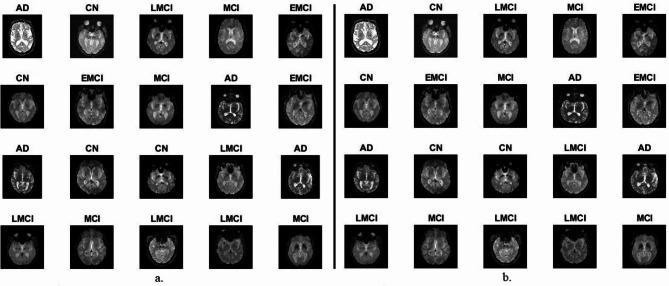

Alzheimer's disease (AD) is a brain disorder that causes memory loss and behavioral and thinking problems. The symptoms of Alzheimer's are similar throughout its development stages, which makes it difficult to diagnose manually. Therefore, artificial intelligence (AI) techniques address the limitations of manual diagnosis. In this study, the images were enhanced and the active contour algorithm (ACA) was used to extract regions of interest (ROI) such as soft tissue and white matter. Strategies have been developed to diagnose AD and differentiate its stages. The first strategy is using XGBoost and ANN networks with the features of MobileNet, DenseNet, and GoogLeNet models. The second strategy is by XGBoost and ANN networks with combined features of MobileNet-DenseNet121, DenseNet121-GoogLeNet and MobileNet-GoogLeNet. The third strategy combines XGBoost and ANN networks with combined features of MobileNet-DenseNet121-Handcrafted, DenseNet121-GoogLeNet-Handcrafted, and MobileNet-GoogLeNet-Handcrafted leading to improved accuracy of the strategies and improved efficiency. XGBoost with hybrid features of DenseNet-GoogLeNet-Handcrafted achieved an AUC of 98.82%, accuracy of 98.8%, sensitivity of 98.9%, accuracy of 97.08%, and specificity of 99.5%.

阿尔茨海默病(AD)是一种导致记忆丧失以及行为和思维问题的脑部疾病。阿尔茨海默病在其整个发展阶段症状相似,这使得手动诊断变得困难。因此,人工智能(AI)技术解决了手动诊断的局限性。在本研究中,对图像进行了增强处理,并使用主动轮廓算法(ACA)提取诸如软组织和白质等感兴趣区域(ROI)。已制定出诊断AD并区分其阶段的策略。第一种策略是将XGBoost和人工神经网络(ANN)网络与MobileNet、DenseNet和GoogLeNet模型的特征相结合。第二种策略是通过XGBoost和ANN网络与MobileNet-DenseNet121、DenseNet121-GoogLeNet以及MobileNet-GoogLeNet的组合特征。第三种策略将XGBoost和ANN网络与MobileNet-DenseNet121-手工制作、DenseNet121-GoogLeNet-手工制作以及MobileNet-GoogLeNet-手工制作的组合特征相结合,从而提高了策略的准确性和效率。具有DenseNet-GoogLeNet-手工制作混合特征的XGBoost实现了98.82%的曲线下面积(AUC)、98.8%的准确率、98.9%的灵敏度、97.08%的精确率以及99.5%的特异性。